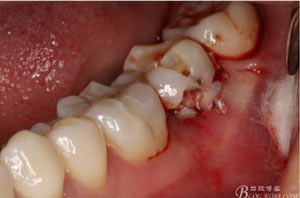

圖6.微創(chuàng)挺拔除37.

圖7.37牙冠碎裂。多生牙壓迫吸收程度嚴(yán)重。